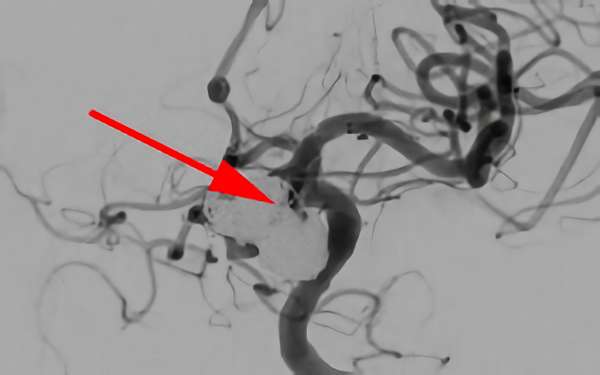

'26年4月

前交通動脈瘤

50代

大阪府の病院

No.1627 手術前

No.1627 手術中

No.1627 手術後